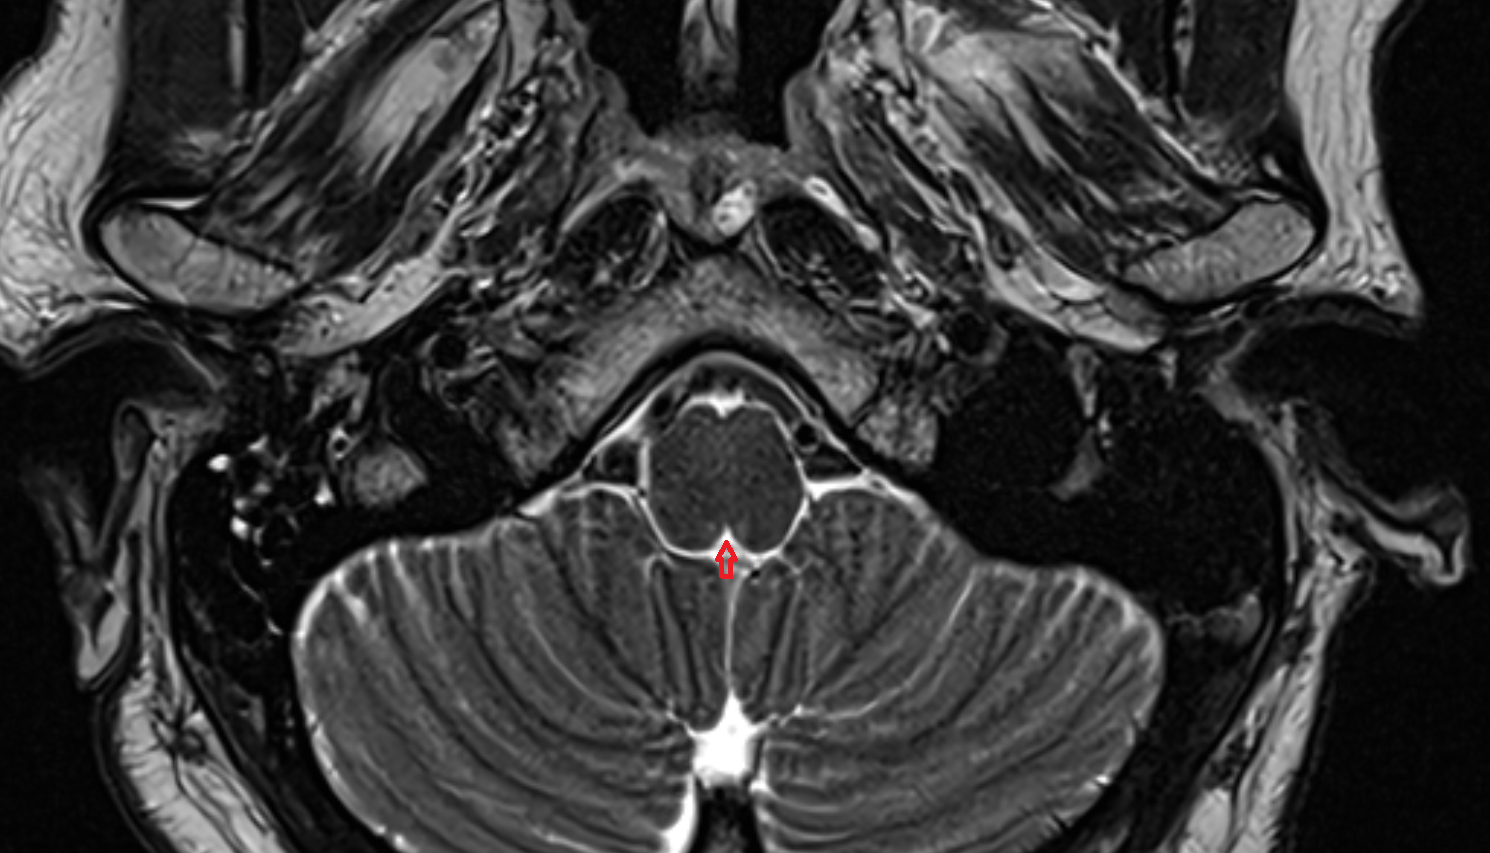

- Lateral aperture of fourth ventricle (foramen of Luschka)